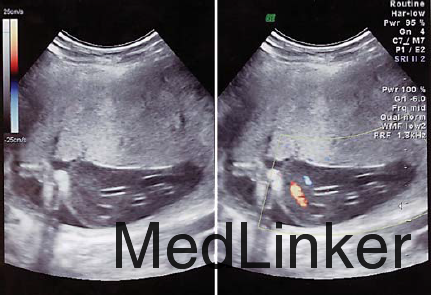

超声提示单活胎和正常羊水量,可见两个脐带囊肿,分别为21*23mm和11*15mm 无血流信号在囊肿里或囊肿周围 无其他畸形可见 孕25周超声提示两个囊肿在增大,分别是30*16mm和17*17mm 胎儿超声提示胎儿腹内脐静脉轻微扩张 孕28周,囊肿附近脐带出现水肿